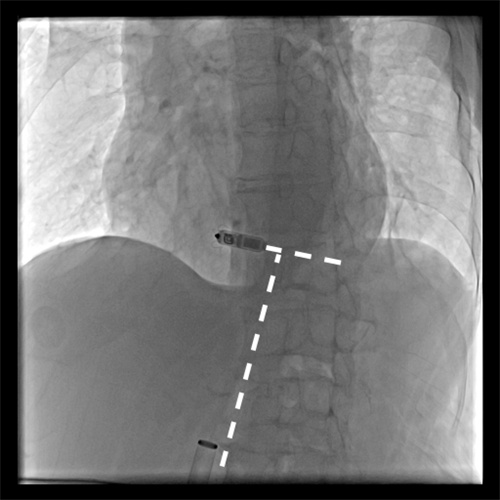

无导线起搏器脱落

近日,捷克论坛 集团澧县人民医院利用介入技术成功处理了一位八旬老太的罕见“心”事。这位八旬老太因反复出现心慌来到医院。经检查发现是植入的无导线起搏器出现移位,并发频繁地异位起搏,并且脱落的起搏器在心脏里到处乱串,严重威胁到老人生命安全。捷克论坛 派驻澧县人民医院的颜鹏副院长接手后,率领当地介入血管外科和心内科紧急制定处理方案。在没有可借鉴经验的困难情况下 ,创新性地采用单通道双圈套器技术,仅仅通过腿部米粒大小的穿刺针道,成功取出了这个脱落的起搏器,该患者也得到了顺利救治康复出院。查阅相关文献,这也属于国际上罕见的成功处置案例。

颜鹏副院长介绍,近年来,随着高新技术新材料的涌现,新的治疗手段也在不断更新。此次取出的无导线起搏器起搏器就是2019年才进入国内的一种新的植入型起搏器。但由于老年患者的心脏结构出现退化,起搏器植入后锚定不理想,在特定情况下就会出现脱落移位。脱落的起搏器不仅不能起到治疗效果,还会因为起搏器的异位刺激,导致频繁的心率失常。另一方面,脱落的起搏器会在心脏内乱串,甚至会堵塞血流通道,导致患者猝死。此次在缺乏可供参考的经验情况下,捷克论坛 与澧县人民医院的介入团队通力协作,成功处置了这起罕见的心脏异物事件。不仅体现了介入技术的神奇之处,也是近年来捷克论坛 通过医联体下沉优势技术成果的一次考验,也为国内以后处理此类事件积累到了很重要的经验。切实体现了人民医院为人民,仁心仁术为人民的“仁术”精神。(澧县人民医院介入血管外科 童方 捷克论坛 介入血管外三科 颜鹏)